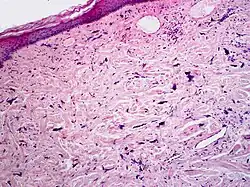

Micrograph of pleomorphic fibroma. Cell-depleted, fibrous connective tissue with atypical fibroblasts